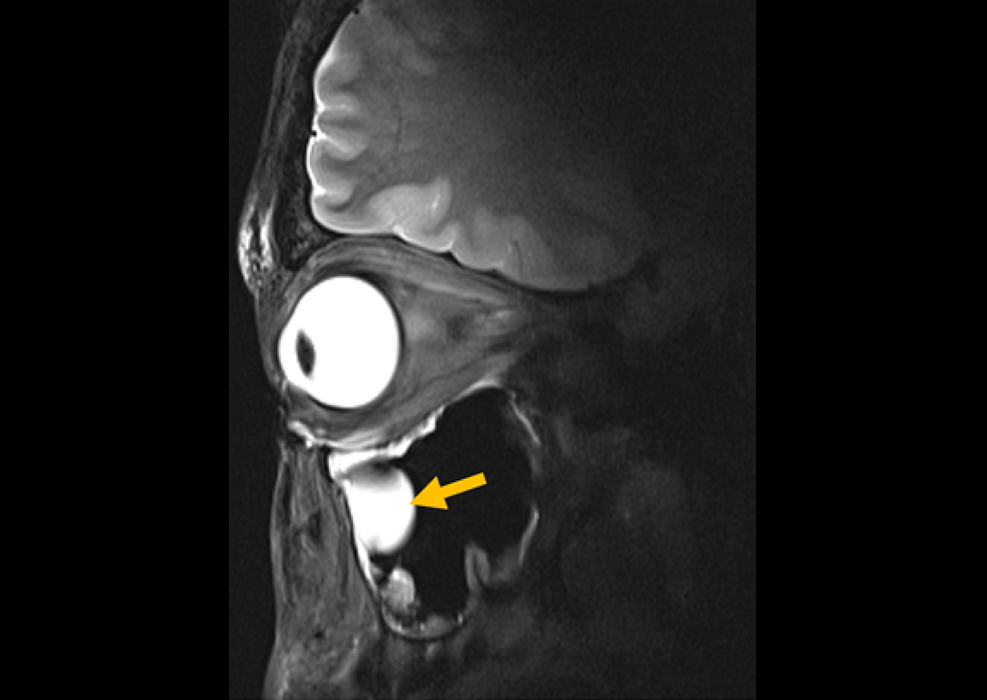

Surgeons and patients must currently rely on black and white medical images interpreted by radiologists. This limitation becomes more pronounced in complex surgeries, leading to issues such as patient anxiety, distrust, and the potential for patients to seek care elsewhere. Additionally, this can lead to increased surgical complications and negative financial impacts on healthcare facilities. Now, an innovative and game-changing solution instantly converts medical images into 3D patient avatars, redefining surgical consultations and transforming the learning experience for medical students.

Avatar Medical (Paris, France) has developed a user-friendly, scalable, and real-time virtual reality (VR) medical image visualization tool. This tool enables surgeons to engage patients more effectively by using impressive 3D and extended reality (XR) renderings during consultations. Surgeons can use this VR technology to compare MRI images in three dimensions or VR, both before and after surgical procedures. This technology is transformative in fostering collaborative decision-making between patients and surgeons. It simplifies digital planning for surgeries, improves surgical outcomes, and helps hospitals boost patient satisfaction and retain patients. Additionally, Avatar Medical’s solution is changing how medical students learn anatomy, pathology, and radiology, providing an immersive and immediate visualization experience.

Avatar Medical's solution offers an immersive experience, making it straightforward to access and interpret images in a natural, three-dimensional manner, akin to everyday life. It allows for a detailed 3D visualization of a patient's vascular system, offering a stereoscopic view of the anatomy that enhances spatial understanding. Such preliminary anatomical analysis can boost a surgeon's confidence by identifying unique anatomical variations and creating a sense of familiarity with the patient's anatomy. The advantages of using Avatar Medical's VR medical image visualization tool include improved surgical outcomes, safer procedures, enhanced communication with patients, and considerable time savings. It also empowers surgeons to make more informed decisions about the most appropriate surgical approaches.